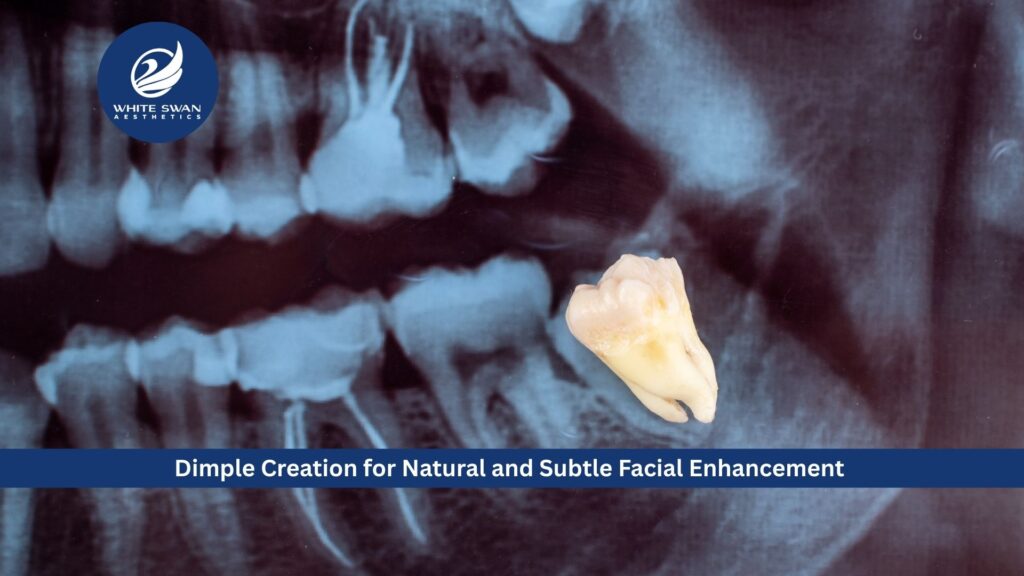

Wisdom tooth extraction is a common dental procedure performed to protect long-term oral health and prevent future complications. Wisdom teeth, also known as third molars, usually emerge in late adolescence or early adulthood. In many cases, there is insufficient space in the jaw for these teeth to erupt properly, leading to pain, swelling, infection, or misalignment of neighbouring teeth. When wisdom teeth become impacted or partially erupted, they can create areas that are difficult to clean, increasing the risk of tooth decay and gum disease. In such situations, this procedure is often recommended to maintain overall oral hygiene and prevent damage to surrounding teeth. A thorough dental evaluation is essential to determine whether extraction is necessary and to plan the procedure effectively.

A proper wisdom tooth extraction begins with a detailed clinical assessment and diagnostic imaging to understand the position and condition of the tooth. This helps the dental professional plan a safe and precise approach while minimising discomfort. Depending on the complexity of the case, the procedure may be performed under local anaesthesia or sedation to ensure patient comfort. Modern extraction techniques focus on gentle tissue handling and controlled removal of the tooth. This approach reduces trauma, swelling, and recovery time. Following wisdom tooth extraction, patients are provided with clear aftercare instructions, including pain management, oral hygiene guidelines, and dietary recommendations to support healing. Most individuals recover within a short period when aftercare advice is followed correctly.